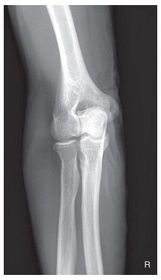

A. medial epicondyle B. trochlea C. coronoid tubercle D. radial head E. capitulum F. lateral epicondyle H. olecranon process